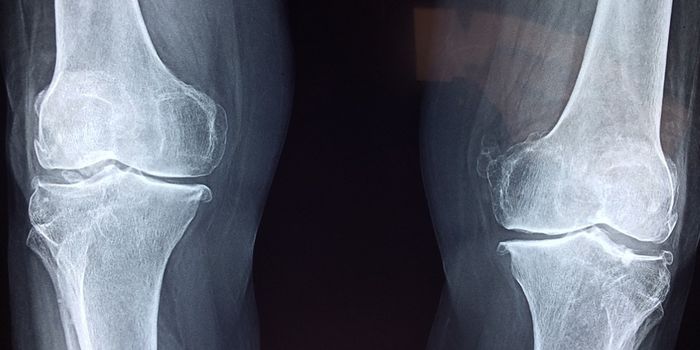

NOV 11, 2021Cell & Molecular BiologyWhile arthritis may not cause pain all the time, when it flares, it tends to recur in the same joints. This can create s ...